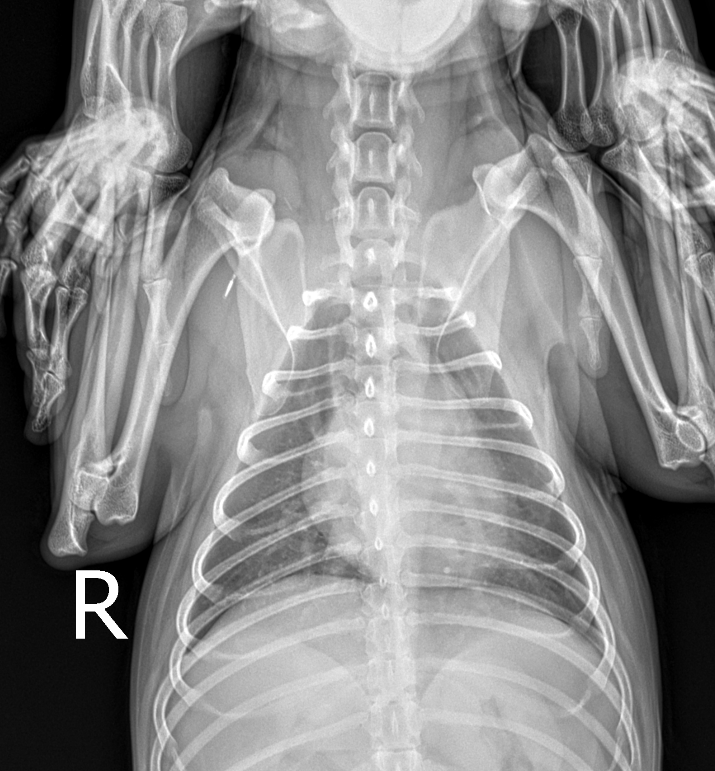

엑스레이를 찍었는데 폐에 물이 찬건가요???

저번주 주말에 찍은 엑스레이입니다.

건강검진 받을 땐 심장이 좀 부어있다고

영양재 주면서 관리만 잘하라고 했어요

올해 검사했을땐 재작년 보다 정말 희미하게

사이즈가 줄었구요ㅠㅠ.. 근데 애기 호흡수가

빨라져서 엑스레이 비교하면서 이것 저것 찾아봤는데

혹시 폐에 물이찬게 아닌가 걱정이 됩니다

엑스레이의 경우 조건을 잘 맞춰고 최대 흡기떄 촬영읋 했을 조건에는 폐가 그렇게 좋아 보이지는 않습니다.

그래도 심장의 크기는 그렇게 커보이지는 않네요

과거 심장병 진단을 받으셨으면 흉부 방사선 외에 심장 초음파도 한번 촬영해보시기 바랍니다.

폐수종을 의심할 수준의 폐 침윤 양상은 관찰되지 않으나

무정형의 간질성 침윤 양상이 관찰되어 노령성변화나 기관지염, 섬유화증 등을 의심할 수 있는 영상입니다.

다만 증상이 비특이적이라 노령성 변화 가능성이 가장 높은것으로 보입니다.